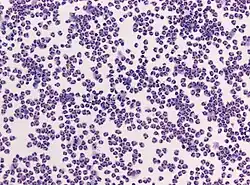

Die Hirn-Rückenmarksflüssigkeit wird mikroskopisch auf rote und weiße Blutkörperchen sowie chemisch auf Protein-, Laktat- und Glukosegehalt untersucht.[3] Eine Gram-Färbung kann zum Nachweis von Bakterien dienen. Allerdings schließt ihr Fehlen eine bakterielle Meningitis nicht aus. Bei einer bakteriellen Meningitis sind nur in 60 % der Fälle, bei vorheriger Antibiotika-Gabe sogar nur bei 40 %, Bakterien mikroskopisch nachweisbar. Die Gram-Färbung zum Nachweis spezifischer Infektionen wie der Listeriose ist zudem unzuverlässig. Eine Bakterienkultur der Probe ist sensitiver, mit ihr können in 70–85 % der Fälle Mikroorganismen nachgewiesen werden, aber es dauert bis zu 48 Stunden, ehe die Ergebnisse vorliegen.[3] Die Unterscheidung der weißen Blutkörperchen gibt bereits Hinweise darauf, ob eine bakterielle (neutrophile Granulozyten überwiegen) oder virale (Lymphozyten überwiegen) Meningitis vorliegt.[3] Allerdings ist dieser Befund im Anfangsstadium der Erkrankung wenig zuverlässig. Deutlich seltener überwiegen eosinophile Granulozyten, was auf eine parasitäre oder Pilzinfektion hinweist.[58]